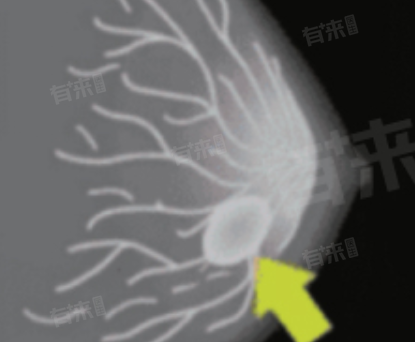

- 在乳腺疾病诊断中,乳腺钼靶有着不可替代的作用。其对微小钙化灶的检出敏感度极高,而微小钙化是早期乳腺癌的重要征象之一。通过观察钙化的形态、大小、分布,医生能够对病变的良恶性进行初步判断。例如,簇状、细小多形性钙化往往提示恶性可能,而粗大、散在的钙化则多为良性表现。

- 对于乳腺腺体密度较低的女性,乳腺钼靶能够清晰显示乳腺导管、腺体、脂肪等结构,有助于发现乳腺结节、肿块等病变。即使是较小的病灶,在钼靶影像上也能通过其边缘、密度等特征与周围组织区分开来,为疾病的早期发现提供有力依据。